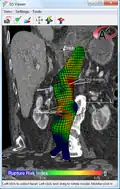

An aneurysm ruptures if the mechanical stress (tension per area) exceeds the local wall strength; consequently, peak wall stress (PWS),[32] mean wall stress (MWS),[33] and peak wall rupture risk (PWRR)[34] are more reliable parameters than diameter to assess AAA rupture risk. Medical software allows computing these rupture risk indices from standard clinical CT data and provides a patient-specific AAA rupture risk diagnosis.[35][36][37] This type of biomechanical approach has been shown to accurately predict the location of AAA rupture.[36][37][38]

Alternative methods of rupture assessment have been recently reported. The majority of these approaches involve the numerical analysis of AAAs using the common engineering technique of the finite element method (FEM) to determine the wall stress distributions. Recent reports have shown that these stress distributions have been shown to correlate to the overall geometry of the AAA rather than solely to the maximum diameter.[72][73][74] It is also known that wall stress alone does not completely govern failure as an AAA will usually rupture when the wall stress exceeds the wall strength. In light of this, rupture assessment may be more accurate if the patient-specific wall stress is coupled together with patient-specific wall strength. A noninvasive method of determining patient-dependent wall strength was recently reported,[75] with more traditional approaches to strength determination via tensile testing performed by other researchers in the field.[76][77][78] Some of the more recently proposed AAA rupture-risk assessment methods include: AAA wall stress;[32][79][80] AAA expansion rate;[81] degree of asymmetry;[74] presence of intraluminal thrombus (ILT);[82] a rupture potential index (RPI);[83][84] a finite element analysis rupture index (FEARI);[85] biomechanical factors coupled with computer analysis;[86] growth of ILT;[87] geometrical parameters of the AAA;[88] and also a method of determining AAA growth and rupture based on mathematical models.[89][90]